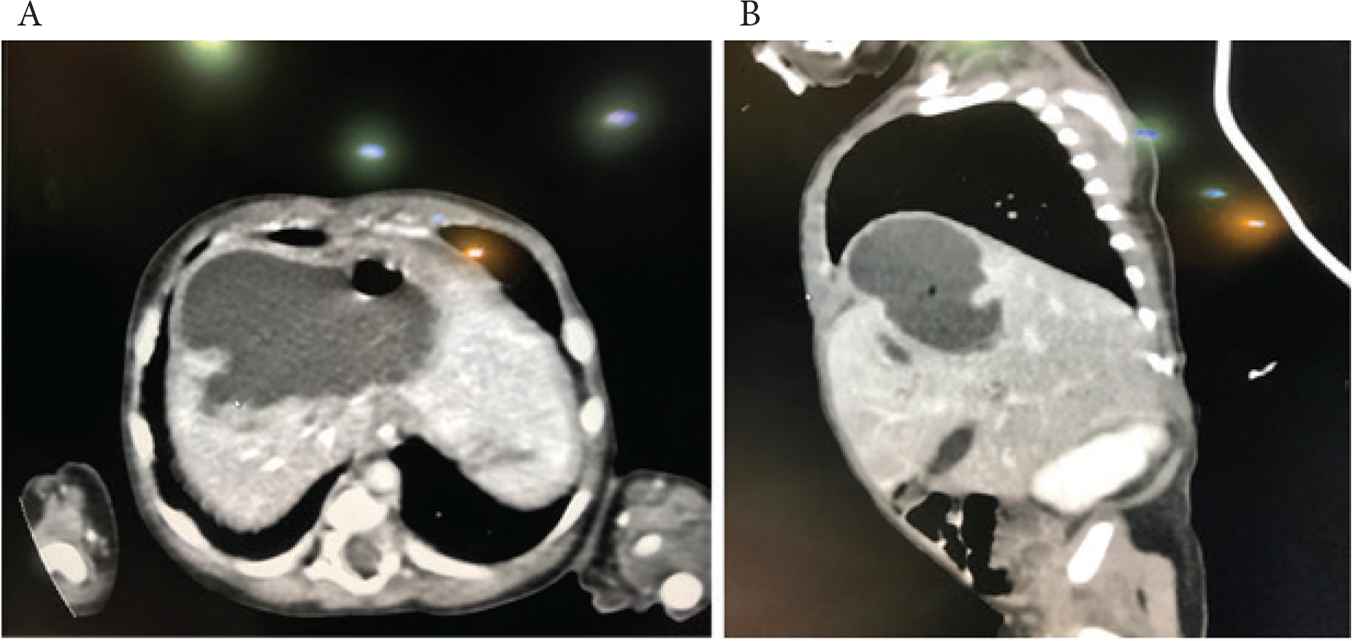

A 16-day-old term, male baby, birth weight 3.1 kg, was transferred to our NICU with sepsis. The Blood Culture and Sensitivity (C/S) was persistently positive for coagulase-negative staphylococci. He was born in the referring hospital by spontaneous vaginal delivery and admitted to their NICU due to meconium aspiration syndrome. He required ventilation for 1 week and an Umbilical Venous Catheter (UVC) was placed in the portal vein at birth. The UVC remained in this position for 6 days with Total Parenteral Nutrition (TPN) running through it. A chest drain was required for right pneumothorax. On admission to our hospital, he had hepatomegaly with raised C-Reactive Protein (CRP). Abdominal X-ray showed enlarged liver with high right-side diaphragm and a small 1 × 1 cm2 air bubble in the liver Figure 1. Abdominal US showed a heterogeneous multiloculated collection in the right liver lobe indenting the right hemidiaphragm, suggestive of liver abscess. Abdominal computed tomography (CT) showed a large multiloculated hepatic abscess with its main bulk in the right hepatic lobe with upper subcapsular extension causing right diaphragmatic elevation and showing multiple air loculi inside suggesting anerobic infection Figure 2A and 2B. The abscess was drained by an emergency laparotomy and an indwelling drain was placed. The C/S from pus was negative, while biopsy from the abscess wall showed nonspecific acute and chronic inflammation with granulation tissue. CRP gradually normalized, the drain was removed, and the baby recovered very well.

(A) Abdominal CT (horizontal view) showing large multiloculated hepatic abscess. (B) Abdominal CT (vertical view) showing large multiloculated hepatic abscess. CT, computed tomography.